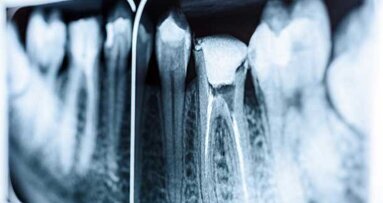

Президентът на ААЕ д-р Гари Р. Хартуел коментира: „Лечението на кореновите канали не заслужава лошата си репутация. Благодарение на напредъка на съвременната анестезия, дигиталната образна диагностика и операционните микроскопи лечението на кореновите канали в наши дни често става бързо и безболезнено“.

Според ААЕ годишно в САЩ се извършват приблизително 15.1 милиона лечения на коренови канали, като 72% от тях (10.9 милиона) са извършени от общи зъболекари, а 25% (4.2 милиона) – от ендодонтисти.